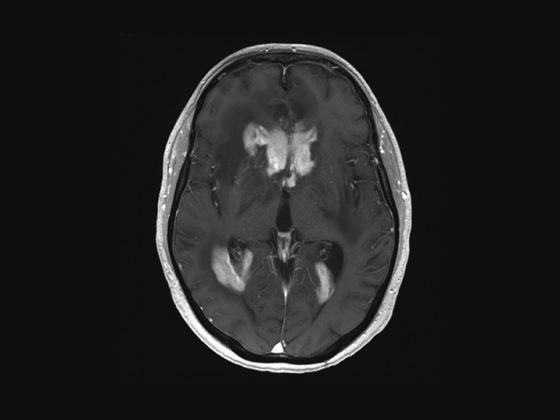

zns-lymphom

• ZNS-Lymphome

Induktion und Konsolidation – welche Wirkstoffe, Schemata und Ziele?

• Fortbildung

• Neurologie

• Onkologie

• Rx

Weiterlesen